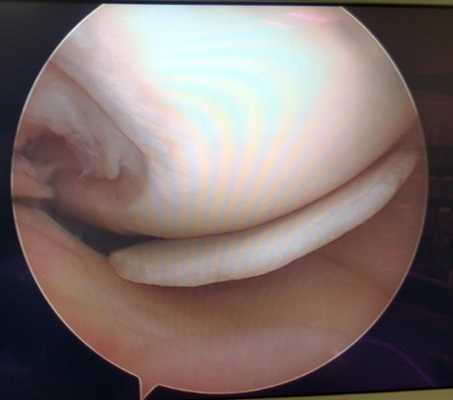

Мениск после обработки по поводу паракапсулярного субтотального разрыва по типу ручки лейки.

Изменения суставного хряща коленного сустава.

Суставной хрящ - гладкая, упругая и прочная соединительная ткань покрывающая кости образующие сустав. Это позволяет костям свободно скользить друг относительно друга в суставном соединении. В случае травм, повышенного износа, некоторых метаболических расстройств хрящ может изнашиваться, вызывая боль и ограничение объёма движений. Артроскопия не лечит артрит или артроз, но может снизить болевой синдром и позволить частично восстановить хрящевое покрытие костей в суставе за счёт таких вмешательств как хондропластика, дебридмент и микрофрактуринг и ряд других.